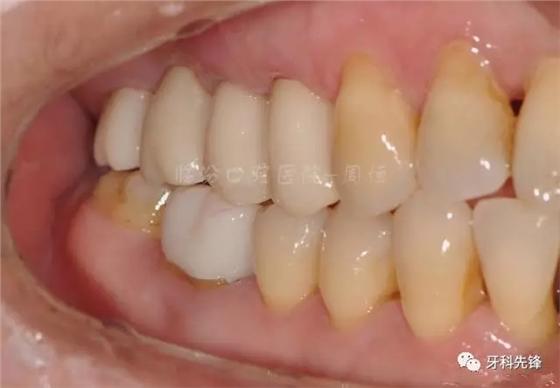

圖20牙體精修咬頜照

640.webp (24).jpg